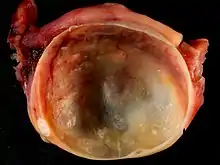

In case an ovarian cyst is surgically removed, a more definite diagnosis can be made by histopathology:

| Type | Subtype | Typical microscopy findings | Image |

| Dermoid cyst | Well-differentiated components from at least two germ layers (ectoderm, mesoderm and/or endoderm).[22] | ![]() | |